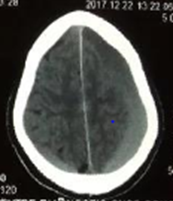

A 57 year old male with past history of mild traumatic brain injury a month ago presented to the emergency neurosurgery department with progressive headache and consciousness disturbance. The neurological examination revealed gait disturbance and left hemiparesis. Brain computed tomography revealed a bilateral chronic subdural hematoma, more predominant on the right fronto-parieto occipital convexity (Figure 1). Routine blood test were within normal limit. A right burr-hole drainage was performed with excellent neurologic recovery in the immediate post-operative period. A week later, the patient symptom reappeared, with a right hemiparesis this time. A stat Brain CT scan disclosed a complete resolution of the right sided hematoma but an increase in the left SDH with a fluid level (Figure 2). A hematologic consult suggested a complete blood coagulation work up that revealed increased D-Dimers and DIC. The patient received FFP and a left sided burr hole drainage was performed with good resolution of symptoms. However, recurrent headache with dizziness appeared 3 days after we removed the drain tube for testing. Repeat brain CT scan revealed reaccumulation of subdural hematoma on both side. The patient was again taken to the Operative room and bilateral subdural space aspiration was performed through both previous holes and the drain were left on both side for 5 days.